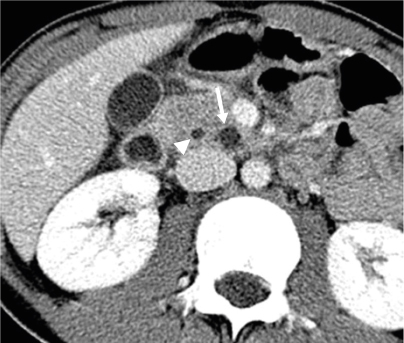

Fig. 2

Abdominal computerized tomography reveals a small cystic mass (arrow) in the pancreatic uncinate process. The adjacent pancreatic duct (arrowhead) is mildly dilated.

The initial preoperative laboratory data revealed an elevated amylase of 153 U/L and a lipase level of 71 U/L. The liver function tests were otherwise normal except for an elevated alkaline phosphatase of 429 IU/L. Abdominal ultrasonography was performed, which showed a lobulated cystic mass in the pancreas (Fig. 1), and subsequent computerized tomography (CT) showed a mildly inflamed pancreas with a 1.2×0.9×1.3 cm-sized low-attenuating cystic lesion with a pleomorphic appearance at the pancreatic uncinate process (Fig. 2). A magnetic resonance imaging (MRI) scan performed later for cystic evaluation showed pancreatic ductal communication with the cystic lesion along with downstream ductal dilatation. Furthermore, mild dilatation of the main pancreatic duct was observed (Fig. 3). The cystic lesion revealed communication with the dorsal duct and congenital anomaly of the pancreatic duct, and pancreas divisum was suspected due to a lack of fusion of the ventral and dorsal ducts and the common bile duct, which joins with the dorsal duct. Therefore, given the suspicion of IPMN and symptoms of pancreatitis, the patient underwent a pylorus-preserving pancreaticoduodenectomy. The histopathology report revealed BD-IPMN with intermediate-grade dysplasia. The depth was limited to the pancreas without invasion of the surrounding adjacent organs. Pancreatic intraepithelial neoplasia was not applicable, and the mucinous glands were of the intestinal type (Fig. 4).